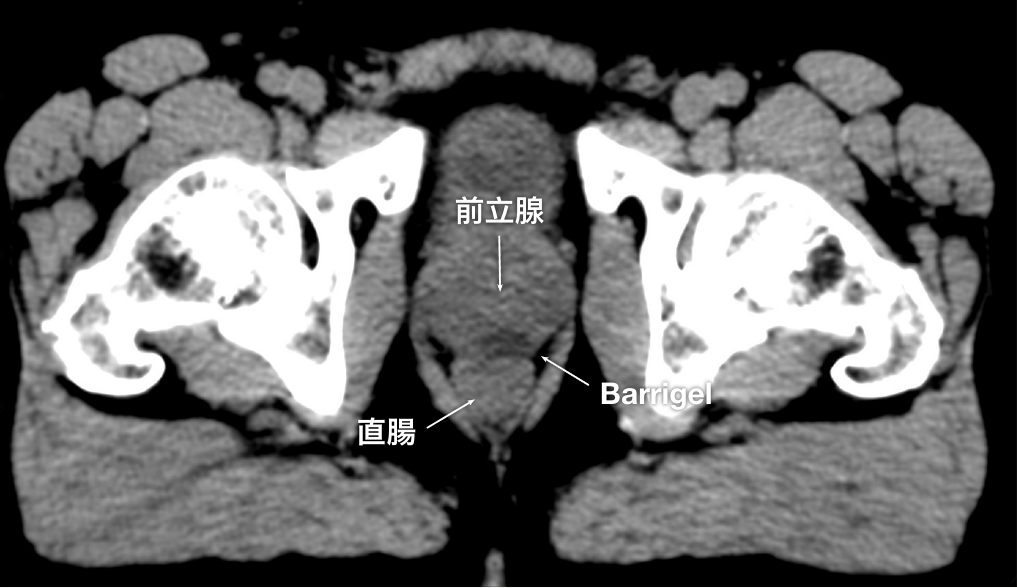

CT画像

CT画像提供:Suraj Singh, MD

Radiation Oncologist, Colorado, United States